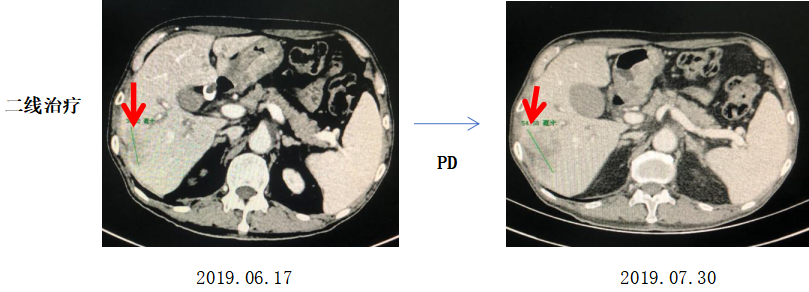

治疗经过:二线治疗

具体治疗方案:

希罗达1000mg bid,d1-14;

奥沙利铂 150mg d1;

赫赛汀8mg/kg,首次,6mg/kg,后续每3周重复。

2019-06-17至2019-07-30,肝内病灶较前增大,2周期XELOX+赫赛汀治疗后肿瘤PD。